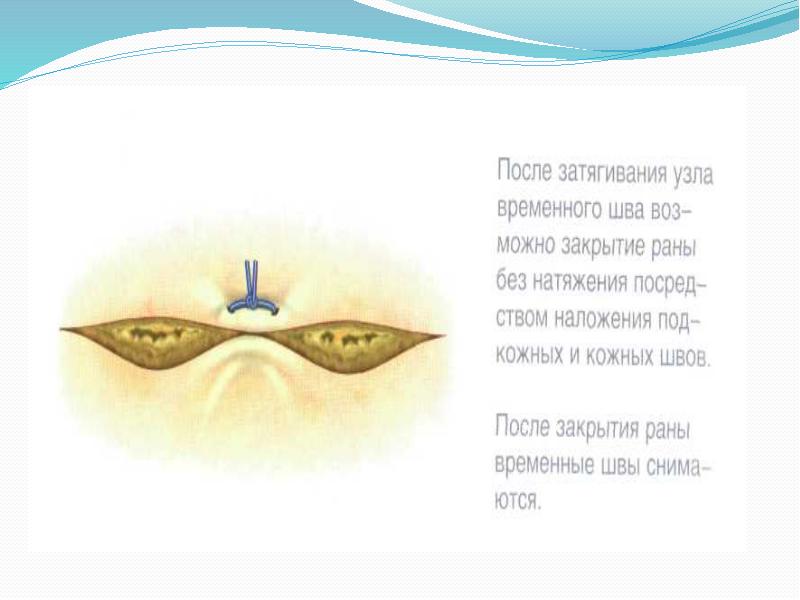

- 46. Зашивание асимметричных ран